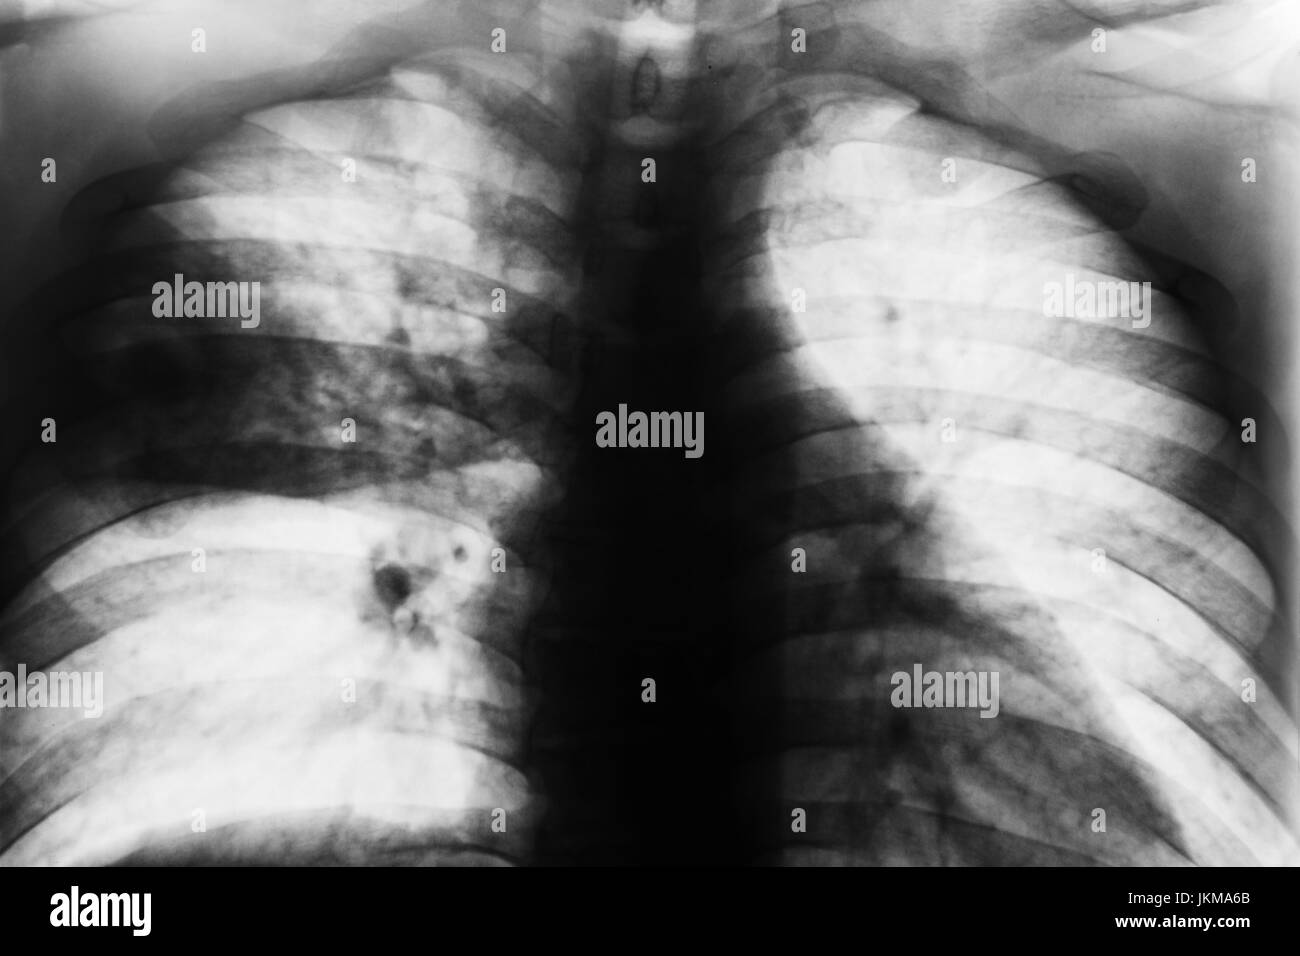

Chest Xray showing diffuse bilateral patchy infiltrates at admission

Lobar Pneumonia . Film chest xray show patchy infiltrate at right Chest X Ray Shows Patchy Infiltrates And Atelectasis The underlying cause (such as. Occurs as a result of complete obstruction of an airway. Atelectases) refers to the collapse or incomplete expansion of pulmonary parenchyma. No new air can enter the portion of the lung distal to the obstruction,. Atelectasis may be used synonymously with. It happens when tiny air sacs within the lung, called alveoli, lose air. Atelectasis. Chest X Ray Shows Patchy Infiltrates And Atelectasis.